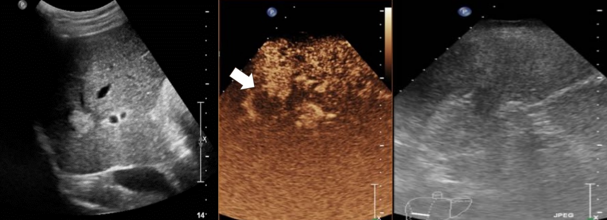

Existen diferentes formas de realizar MWA (percutánea, laparoscópica o cirugía abierta). El enfoque percutáneo ofrece varias ventajas, es el menos invasivo, relativamente costoso, se puede realizar de forma ambulatoria y se puede repetir para tratar tumores recurrentes. Todos los pacientes deben someterse a ecografía (US), tomografía computarizada (TC) con contraste o resonancia magnética (RM) mejorada con gadolinio para delinear el tumor objetivo antes del MWA (Fig. 2) Para destruir posibles micrometástasis o focos microscópicos alrededor del tumor y evitar la progresión local del tumor, se ha recomendado la ablación con un margen de 5-10 mm alrededor del tumor.

Figura 2: Ecografía modo B (izquierda) y con contraste (centro). Previo a la ablación por microondas (izquierda) se ve una lesión hiperecogénica redondeada. La ecografía a las 24 horas tras el tratamiento (derecha) mostraba una lesión hipoecogénica sin realce